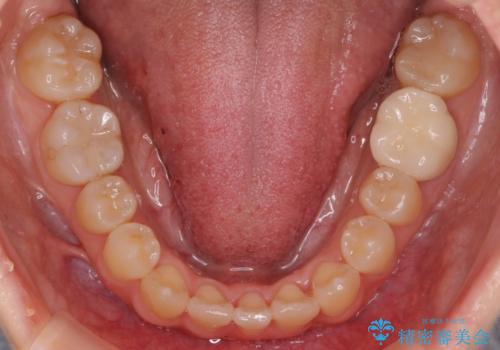

- 八重歯を治したいと来院。

古典的な治し方ですと上下左右4本抜歯してワイヤー矯正です。

今回は口元も出ていないうえに、右上のみの八重歯のため奥歯を後ろに下げて治療しました。

ただし、下の前歯は入りきらない為1本のみ抜歯しています。